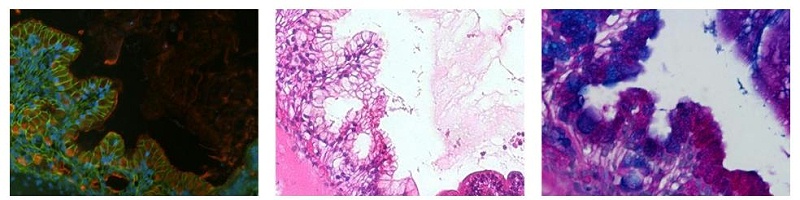

類器官培養(yǎng)

成熟類器官